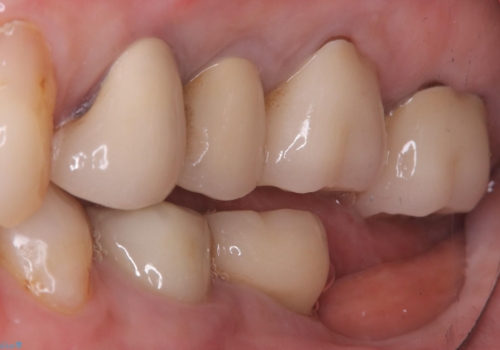

- 主訴:昔入れた被せものの境目の黒いところが気になる

クラウンの不適により境目に汚れが溜まり、黒く見えていました。

古いクラウンを除去し、不適部位から中で広がっていたカリエスを除去したのちCRにて築造、仮歯を経てセラミッククラウンをセットしています。